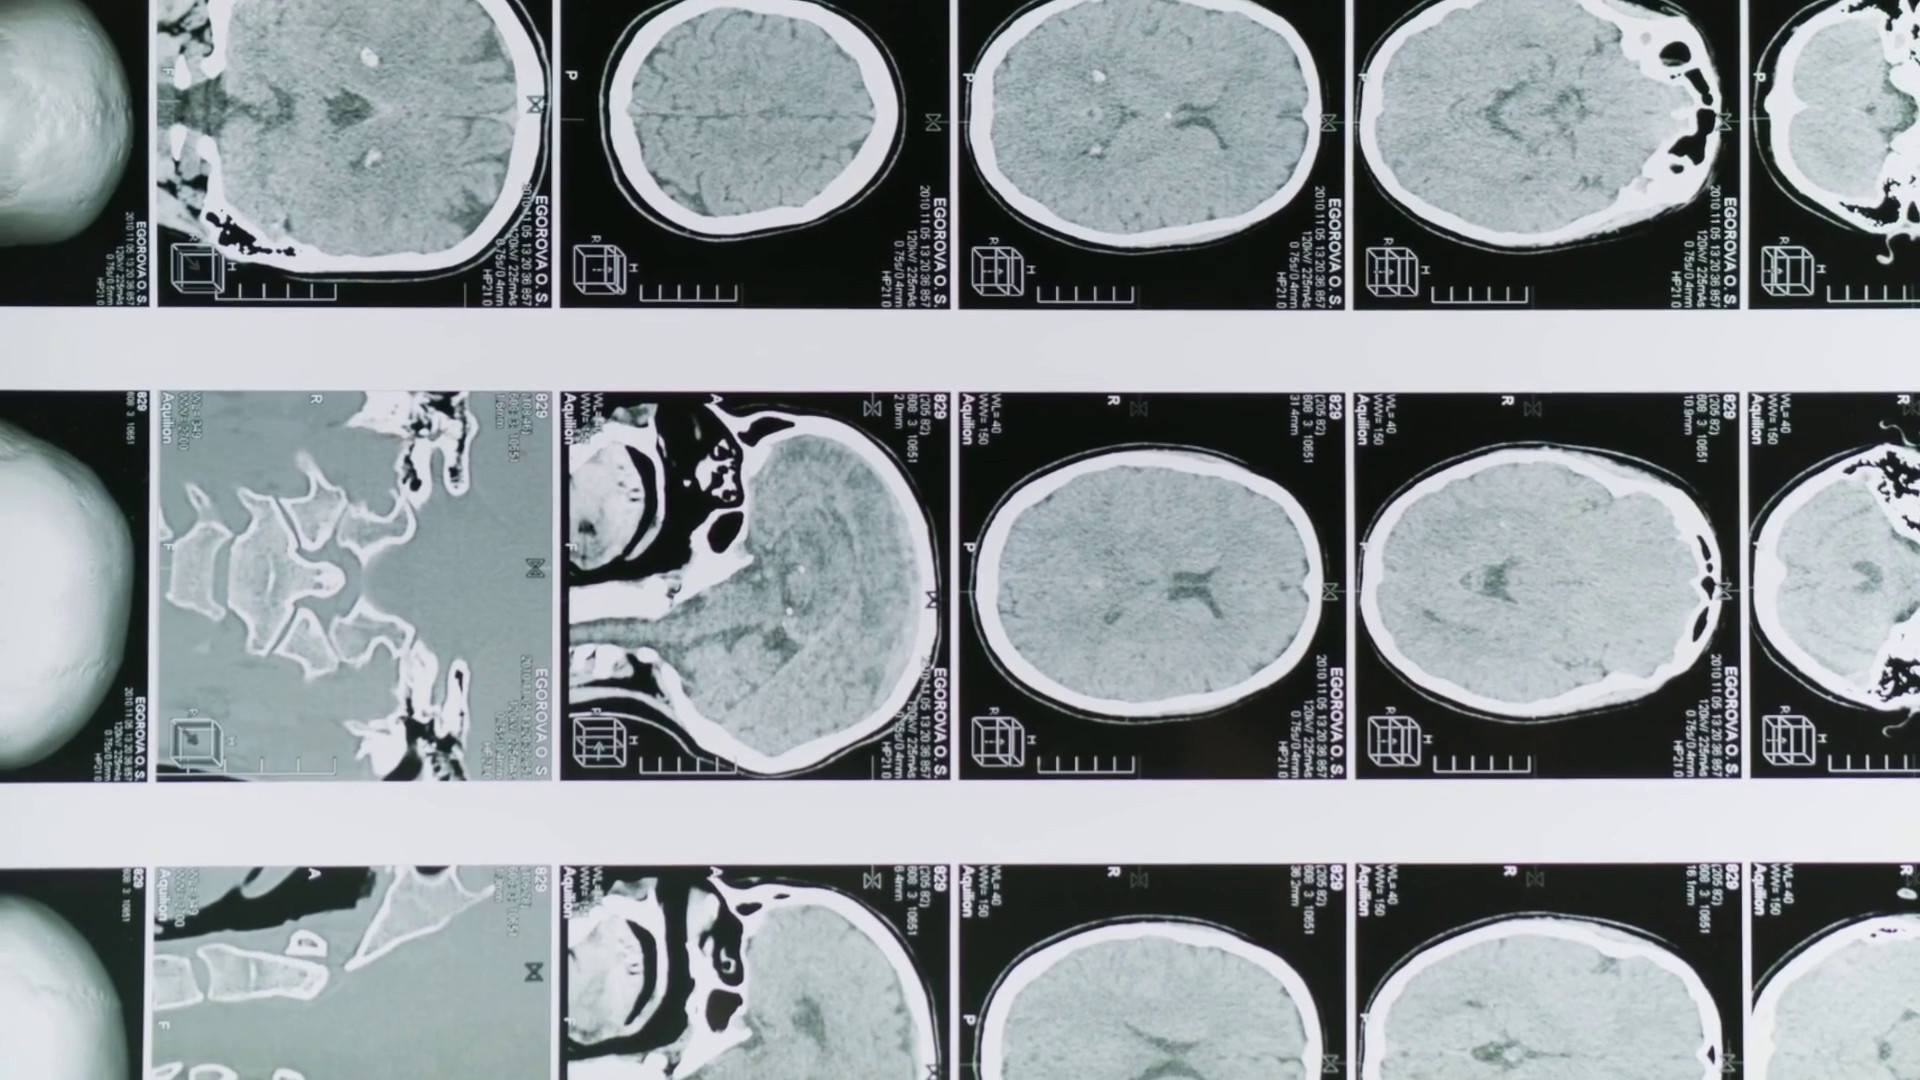

Glioblastoma, le molecole naturali migliorano la chemioterapia

Glioblastoma, le molecole naturali migliorano la chemioterapia..